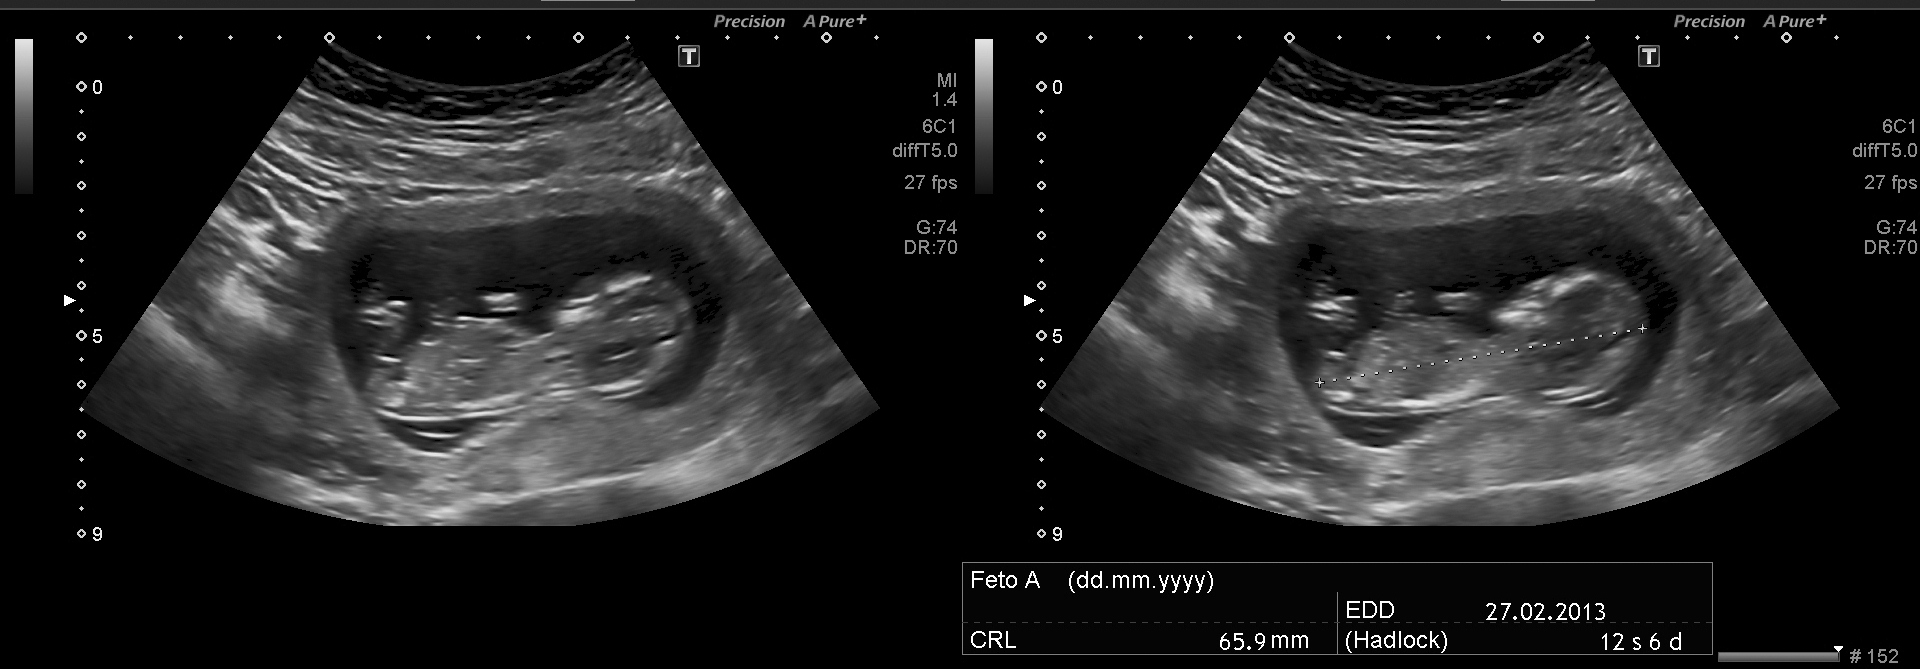

UAttachment 5420Utrasound at 12 weeksyou think it is boy or girl? Now I put the photo of ultrasound ... tell me what you think